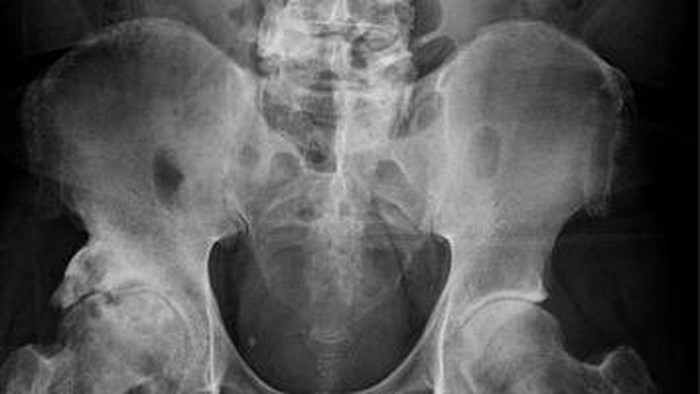

Mereka juga melakukan rontgen panggul untuk mencari kemungkinan adanya fraktur panggul. Sebaliknya, mereka menemukan adanya pertumbuhan tulang di tempat yang tidak terduga, yakni penis pria tersebut.

"Terlihat pasien memiliki 'kalsifikasi yang luas seperti plak' di sepanjang alat kelaminnya," tulis para peneliti, dikutip dari Live Science.

Dari hasil pemeriksaan, dokter mendiagnosis pasien tersebut dengan osifikasi penis. Hal tersebut merupakan kondisi saat garam kalsium terkumpul di jaringan organ, membentuk struktur ekstraskeletal yang sangat mirip tulang.